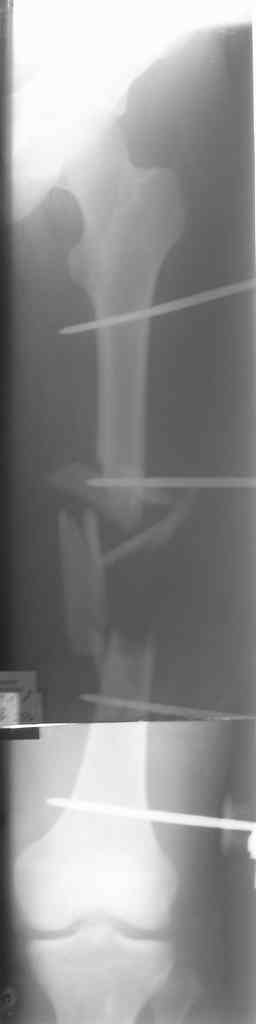

Вчера сделали снимки - положение отломков и осколков вот такое. На перевязке: из раны небольшое кол-во сгустков крови с примесью гноя , хотя бедро спокойное, гипертермии ни локальной ни общей нет. Вопрос: как быть дальше? открывать рану, "чистить" ее, наладить ее перфузию АС, АБ? что делать с осколками, попробовать перекрыть область перелома с фиксацией основных отломков аппаратом. Или осколки убрать и состыковать основные отломки с жутким укорочением и большими проблемами при зашивании раны?